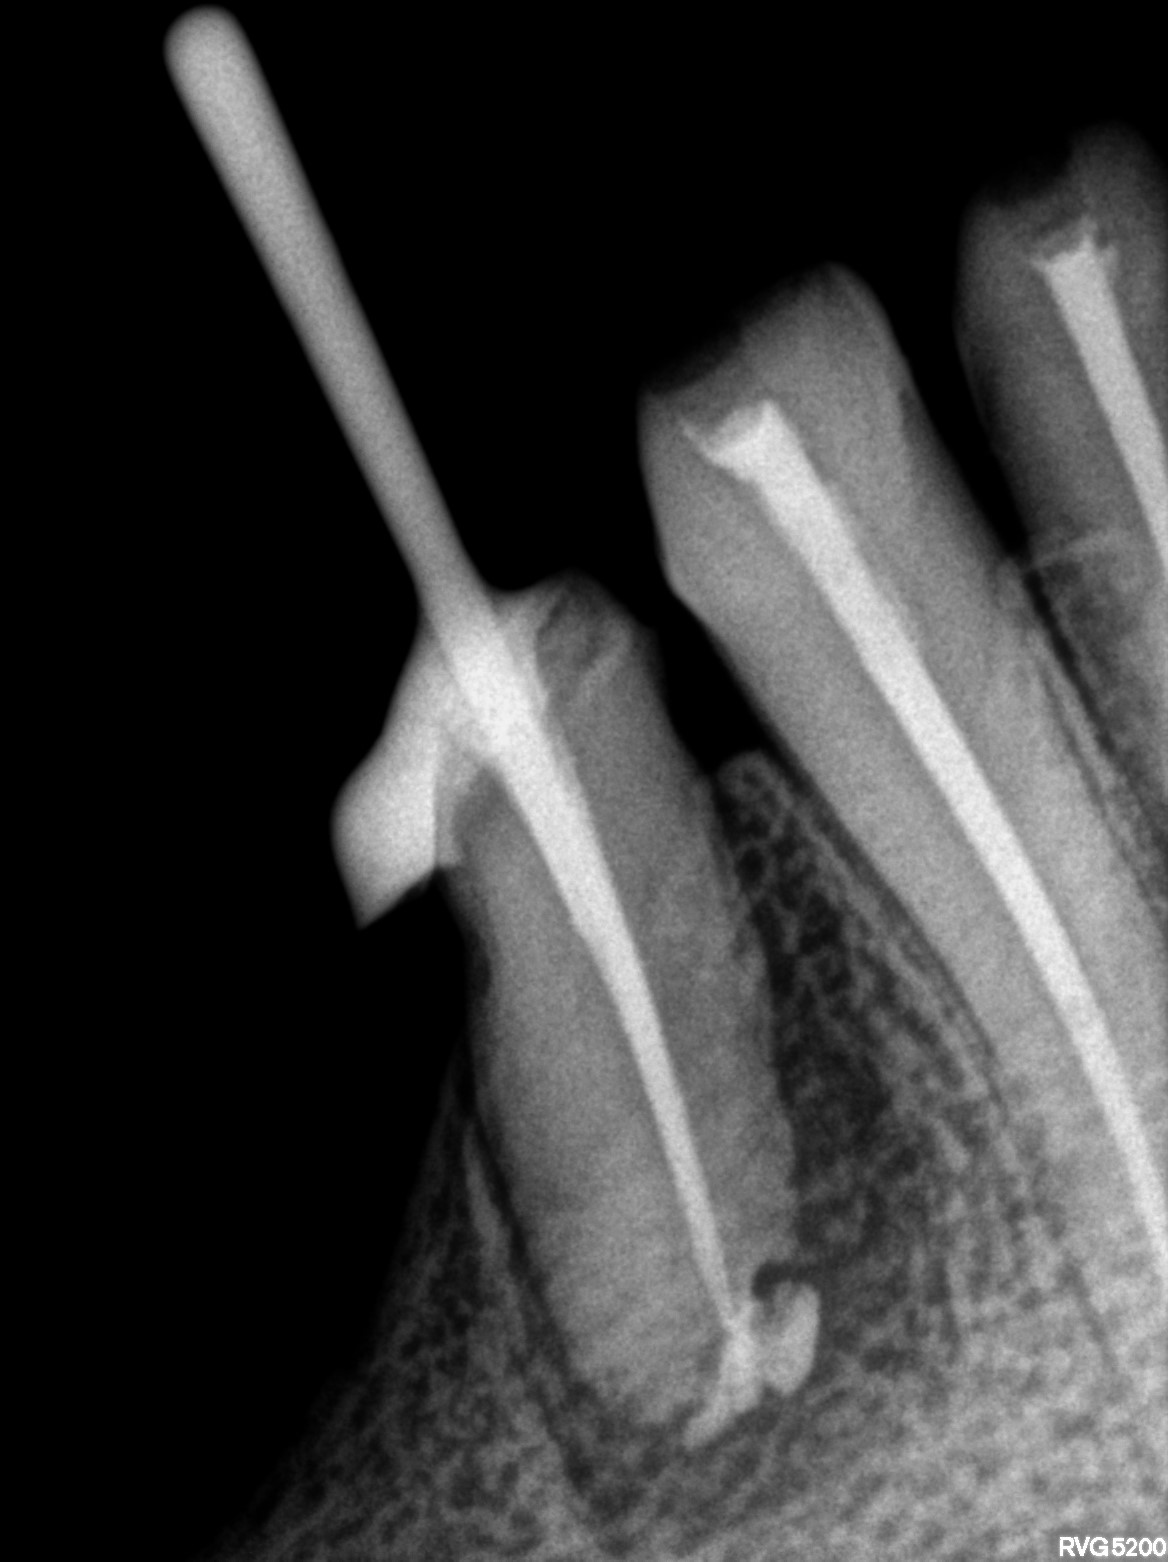

Dental Radiographs FHIR: DocumentReference · LOINC 24641-7

xray_1763362538_0.jpg

24641-7